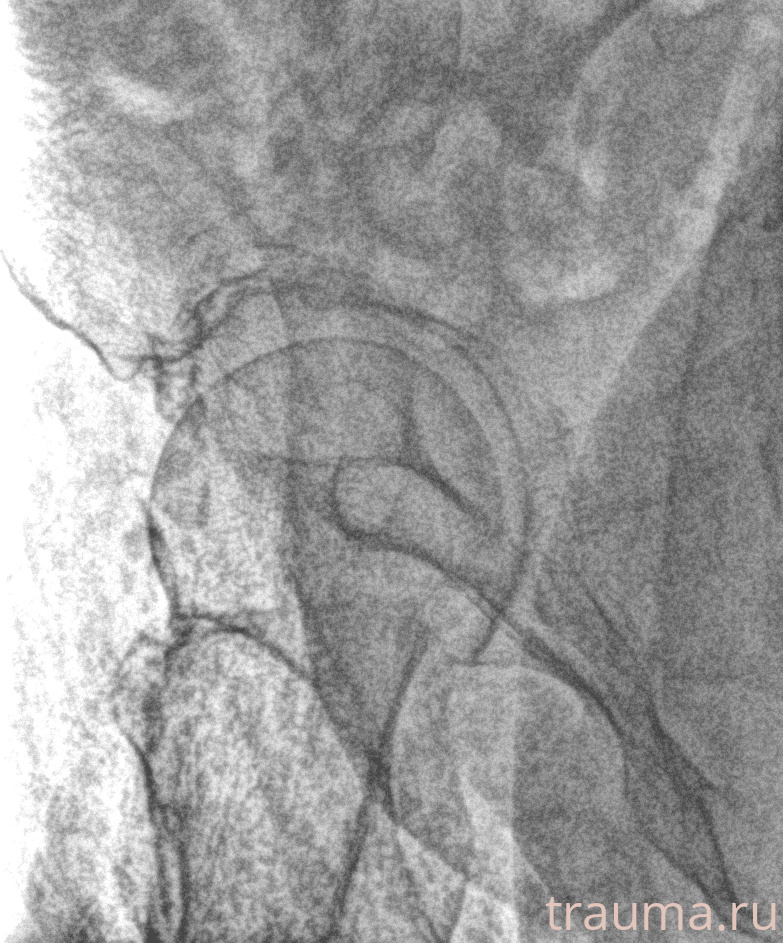

Рентген на дому: по вашему адресу приезжает врач-рентгенолог, травматолог-ортопед с мобильным рентгеновским аппаратом, проводит диагностику травмы или заболевания, делает необходимые рентгенограммы, дает рекомендации по дальнейшему лечению. Получить качественные снимки в домашних условиях возможно благодаря уникальной методике, разработанной МосРентген Центром для института  Склифосовского